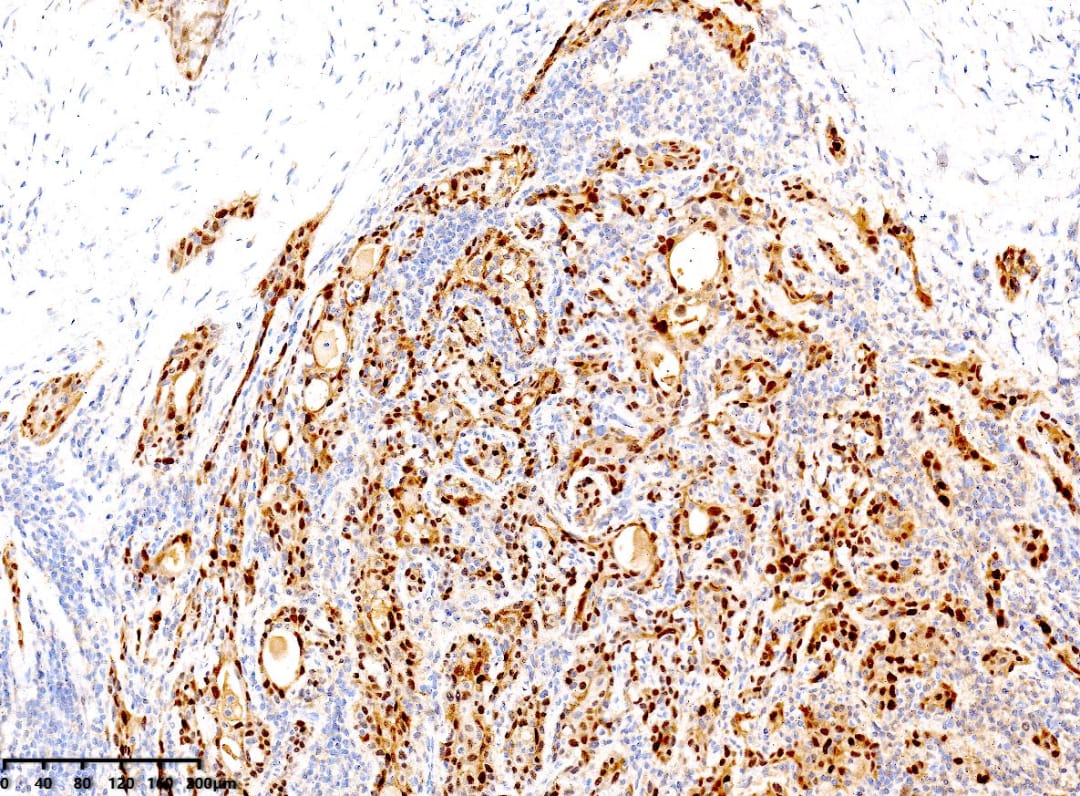

免疫组化与分子特征

免疫组化结果显示:CK19(+)、p40(+)、p63(+)、PAX8(+)、TTF-1(+)、CK5/6(+)、CyclinD1(+)。值得注意的是,BRAF V600E(部分+)和p53突变型阳性,Ki67阳性指数约15%。这些分子标记物对于确诊和鉴别诊断至关重要。

CK5/6(+)

p40(+)

镜下可见肿瘤细胞呈实性巢状、条索状排列,部分癌巢周边细胞呈栅栏状排列,可见细胞间桥、角化珠和单个细胞角化。肿瘤细胞胞质嗜酸性,核深染,核分裂象多见。间质常伴有纤维组织增生和淋巴细胞浸润。免疫表型上,肿瘤细胞通常表达PAX8、CK19、CK-H、TTF-1、CyclinD1,以及鳞状细胞标记物CK5/6、p40、p63。大部分病例可检测到BRAF V600E突变。分子遗传学方面,TP53及BRAF V600E突变是甲状腺鳞状细胞癌的常见特征。